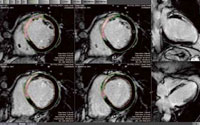

心臓の弁の動きをなめらかに表示

4D心臓フュージョン